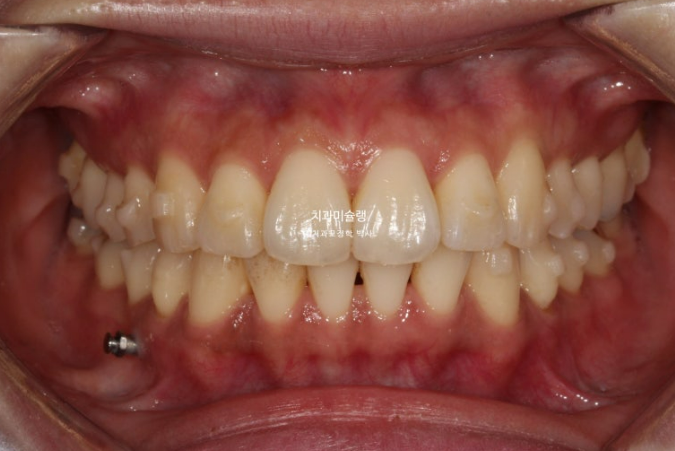

두번의 재제작을 통해 정확히 맞아진 중심선

어금니 교합은 물샐틈 없는 1급 교합관계를 보입니다.